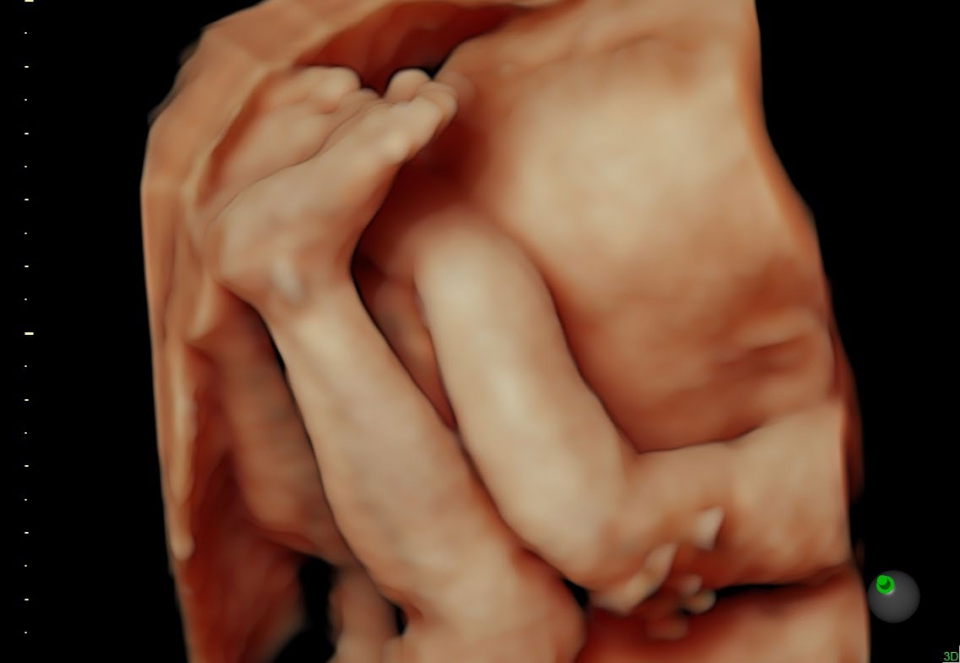

УЗИ аппарат Voluson S10 позволяет проводить обследования высочайшего уровня с максимальной точностью диагностики. Благодаря технологии Voluson Core Architecture достигнут высокий уровень качества изображений с возможностью последующей обработки и анализа даже после проведения скрининга. Технология HDlive делает изображения удивительно реалистичными и объемными.

• HDlive в 3D и 4D - режим перемещаемого виртуального источника освещения - "виртуальная фетоскопия"